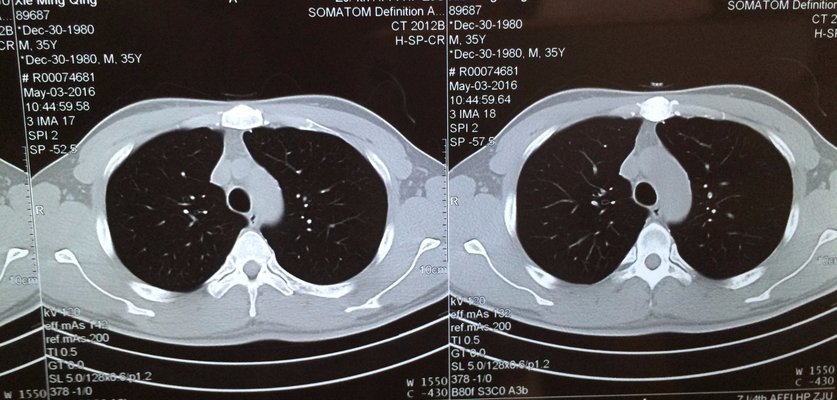

Infantile pneumonia is the first cause of death in hospitalized children in China! Bronchopneumonia accounted for more than 90% of pneumonia. Bronchopneumonia, also known as lobular pneumonia, can be caused by a variety of pathogens such as virus, bacteria or Mycoplasma invading through the bronchus, causing inflammation of bronchioles and alveoli. Often secondary to other diseases, such as bronchitis, bronchiectasis, upper respiratory tract virus infection. How to prevent bronchopneumonia? Let's talk about my views.